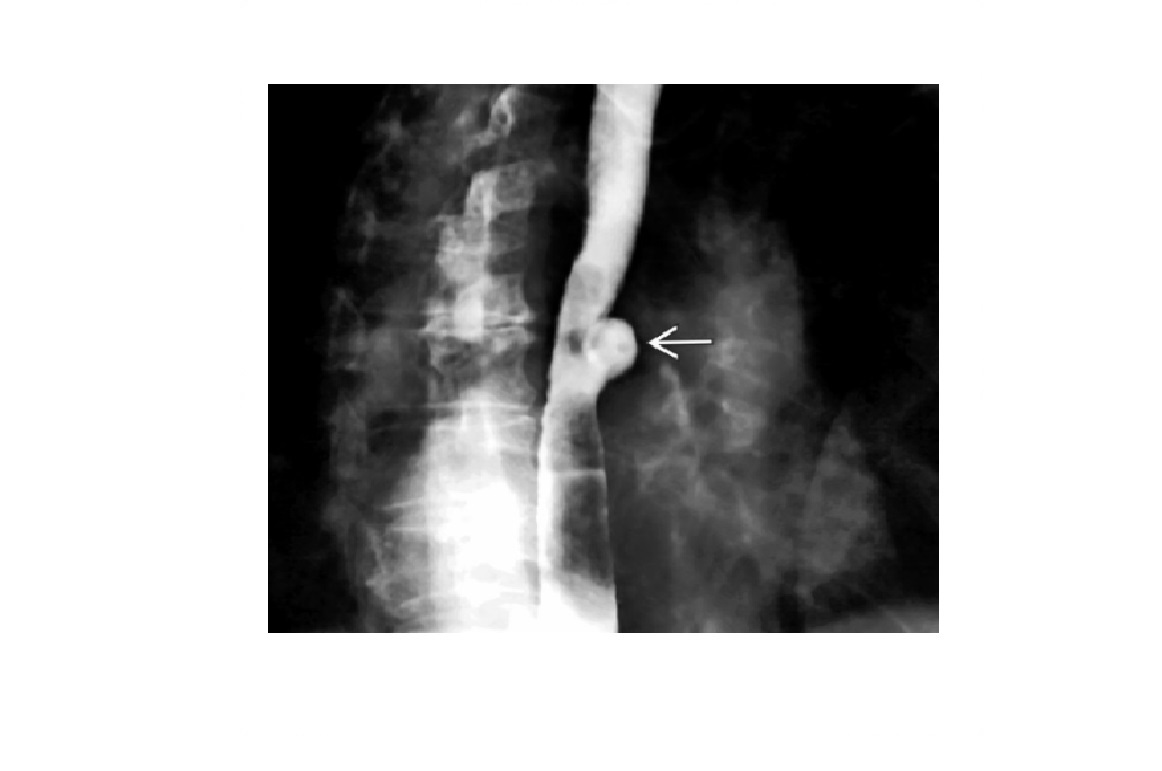

Traction diverticulum

Dysphagia in elderly person. Previous TB.

Barium-filled tented or triangular outpouching in the mid oesophagus

Acquired condition due to subcarinal or perihilar granulomatous lymph node pathology (TB, histo)

External force on oesophageal wall, such as mediastinal inflammation, that adheres and pulls on oesophageal wall